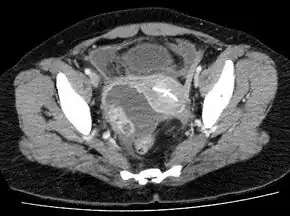

A tubo-ovarian abscess to the person's right of the uterus. The uterus contains an IUD.[14]

Laparoscopy and other imaging tools can visualize the abscess. Physicians are able to make the diagnosis if the abscess ruptures when the woman begins to have lower abdominal pain that then begins to spread. The symptoms then become the same as the symptoms for peritonitis. Sepsis occurs, if left untreated.[15]: 103  Ultrasonography is a sensitive enough imaging tool that it can accurately differentiate between pregnancy, hemorrhagic ovarian cysts, endometriosis, ovarian torsion, and tubo-ovarian abscess. Its availability, the relative advancement in the training of its use, its low cost, and because it does not expose the woman (or fetus) to ionizing radiation, ultrasonography an ideal imaging procedure for women of reproductive age.[8]